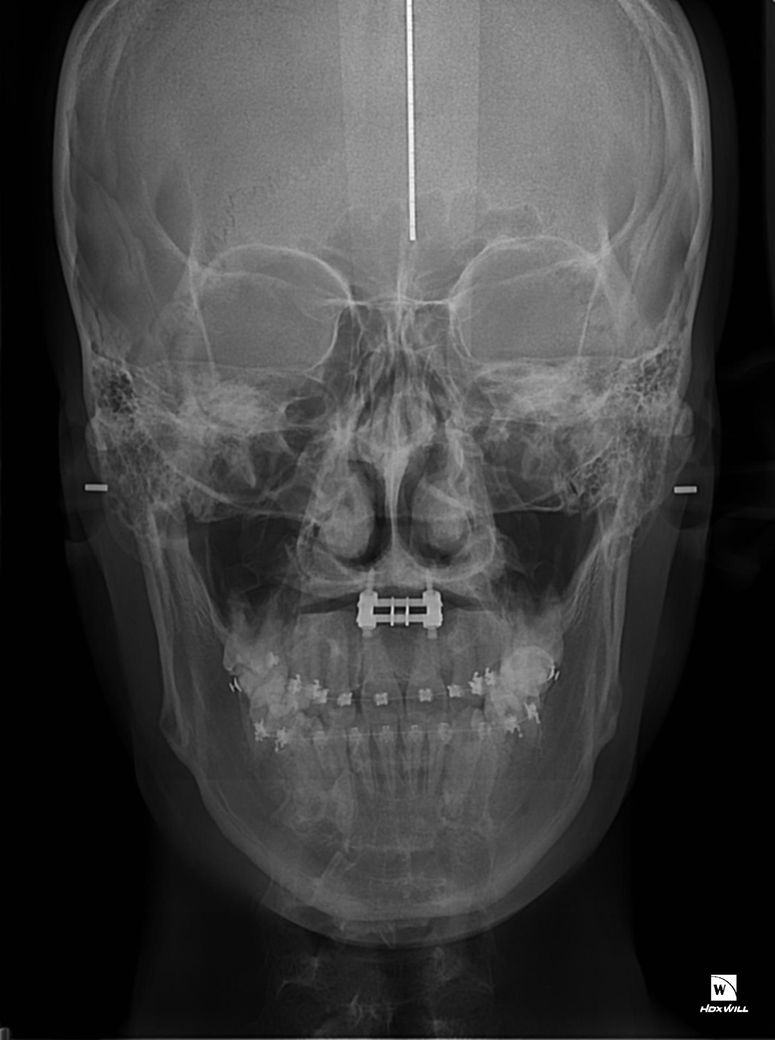

왼쪽사진이 악궁확장돌리기전이고 오른쪽사진이 악궁확장 돌리기후인데 왼쪽사진 엑스라이상에 광대뼈가 하얀색 이어로드에 닿지않고 공간이 널널한반면에 두번째사진에서는 하얀색이어로드 위치를보시면 광대뼈가 닿아있습니다 저만큼 광대뼈가 자랐다는건가요?

• 2번 째 사진